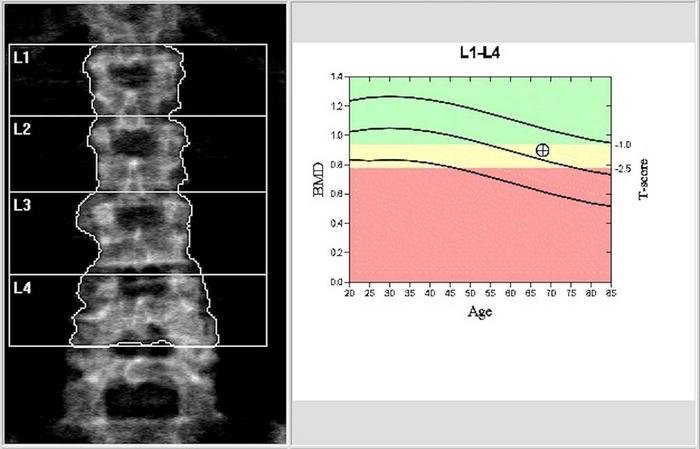

Die Ergebnisse zeigten, dass die Einnahme von Levothyroxin mit einem größeren Verlust an Knochenmasse und Knochendichte des gesamten Körpers verbunden war – selbst bei Teilnehmern, deren TSH-Werte im Normbereich lagen – über einen Beobachtungszeitraum von durchschnittlich 6,3 Jahren. Dies galt auch, wenn der TSH-Ausgangswert und andere Risikofaktoren berücksichtigt wurden.

„Unsere Studie deutet darauf hin, dass die Einnahme von Levothyroxin selbst bei Einhaltung der aktuellen Leitlinien mit einem stärkeren Knochenschwund bei älteren Erwachsenen verbunden zu sein scheint“, sagte Dr. Shadpour Demehri, Co-Autor der Studie und Professor für Radiologie an der Johns Hopkins University.